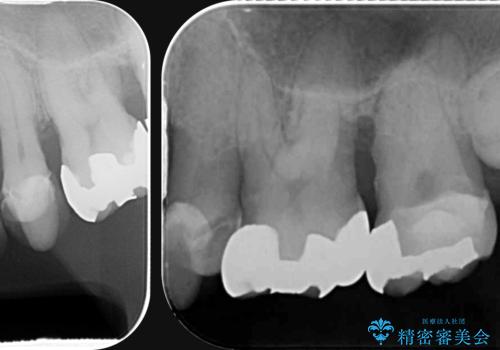

- 「全体的に歯が揺れ、今後の歯の健康に不安がある。歯周病の治療を受けたい。」、と来院されました。

精密検査の結果、重度の歯周病が認められ大きな骨の吸収を認めました。

予後の悪く保存の難しい歯を抜去し、骨の造成を含んだインプラント治療を計画します。